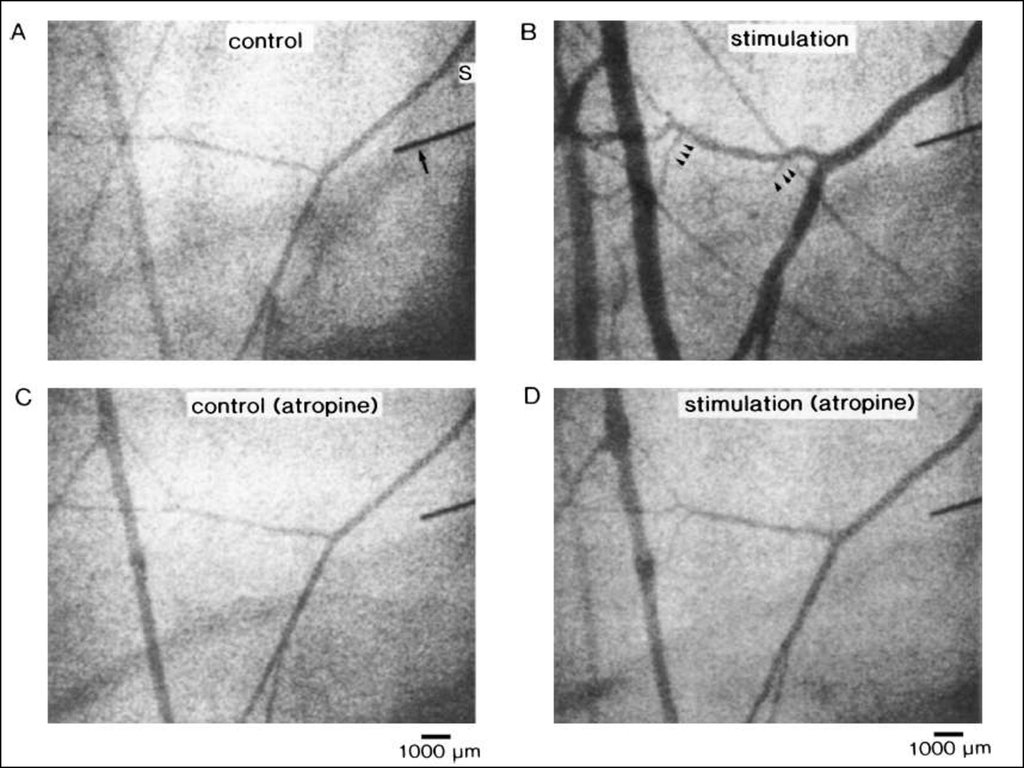

Individual records from two subjects during periods of severe mental stress. A, in a

patient with a unilateral cervical sympathectomy, mental stress (hatched bar) evoked

profound increases in forearm blood flow in the normal arm. These increases in forearm

blood flow were absent in the sympathectomised forearm. B, a second subject was

studied with normal innervation to both upper extremities. Atropine given selectively to

one forearm blunted but did not eliminate the vasodilator responses to severe mental

stress. Adapted from Blair et al. (1959).